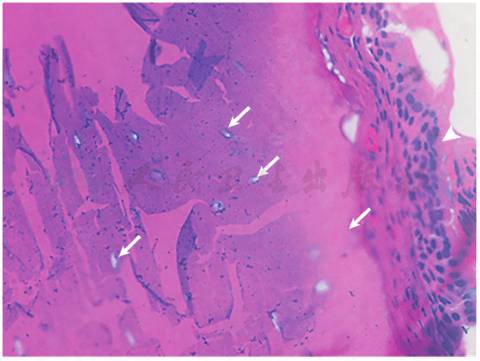

病理报告:(气管壁活检及电切)气管、支气管骨化病(图2)。

图2 HE染色(×100)示:支气管壁黏膜上皮鳞状化生(箭头),黏膜下骨化及软骨组织骨形成,可见散在支气管软骨细胞(白箭)